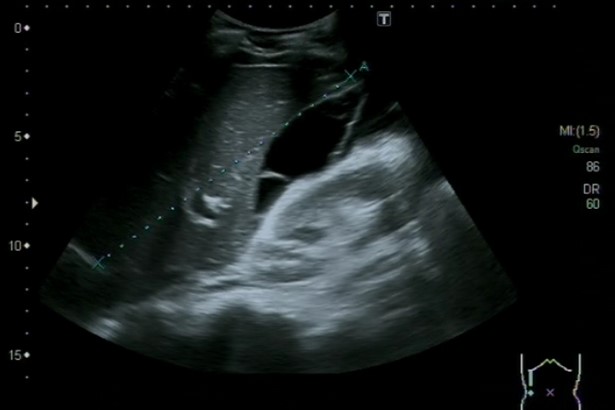

Hallazgos ecográficos

Ascitis a estudio, sugestiva de peritonitis tuberculosa

La ecografía clínica es una herramienta esencial en el diagnóstico de la ascitis. Permite la identificación y cuantificación precisa del líquido, además de evaluar su distribución. La realización de paracentesis guiada por ecografía es fundamental para establecer la causa subyacente de la ascitis, permitiendo obtener muestras de líquido para su análisis. La combinación de la ecografía y la paracentesis mejora la precisión diagnóstica y guía la atención médica apropiada.